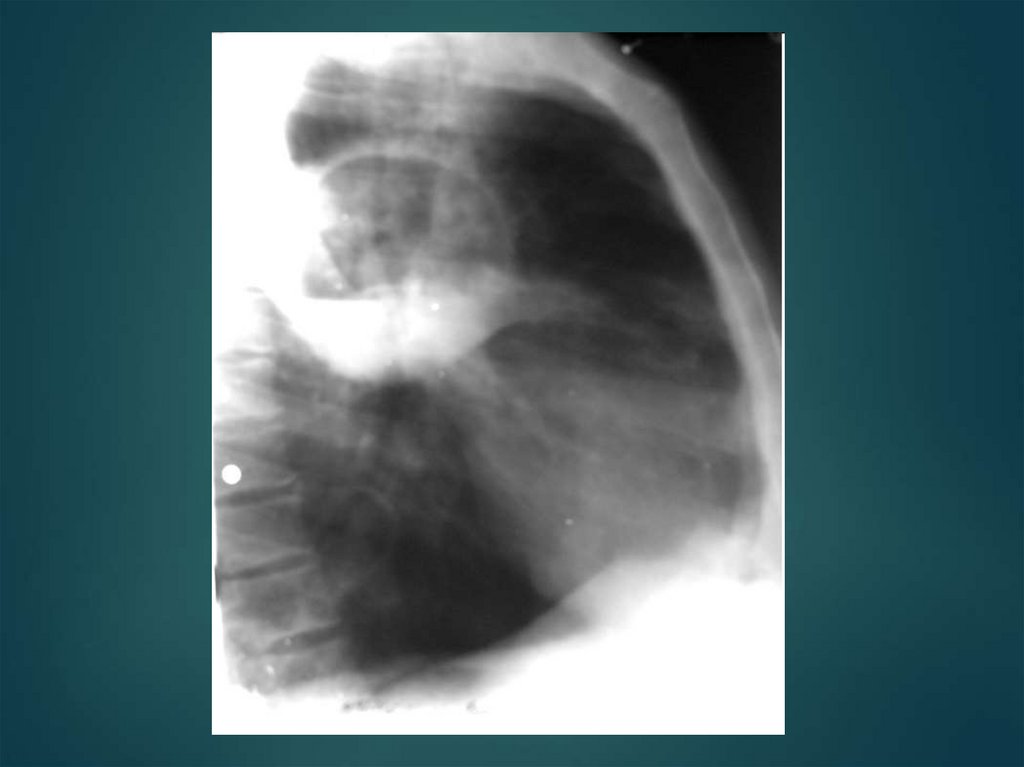

62. Гемоторакс–

скопление крови в плевральной полости в

результате внутреннего кровотечения при

ранении ткани легкого, повреждении

межреберных артерий (переломы ребер).

64. Клиника:

зависит от количества излившейся крови и темпа

внутриплеврального кровотечения.

Небольшое количество крови вызывает боль в

груди, кашель.

По мере скопления крови возникает одышка,

цианоз, вынужденное сидячее положение

пациента.

Значительная кровопотеря сопровождается

тахикардией, появляется бледность кожных

покровов, слабость, боль в грудной клетке,

падение артериального давления, учащение

пульса, кашель.

При аускультации ослабление дыхания, при

перкуссии притупление перкуторного звука внизу

на стороне поражения.